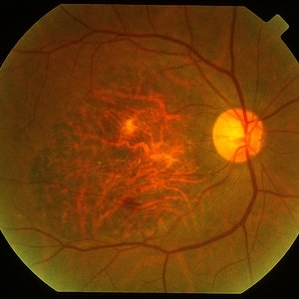

Active Choroidal Neovascularization With Subretinal Hemorrhage

Nov 25 2013 by Maurice F. Rabb

Active choroidal neovascularization with subretinal hemorrhage.

Condition/keywords: choroidal neovascularization (CNV), subretinal hemorrhage